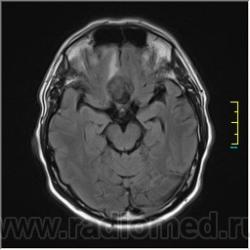

Ax T2:

Ax T2 Flair:

частично функционирующая аневризма

Иначе говоря, аневризма с хронической геморрагией, т.к. мы видим фракции крови различного возраста.

Постепенное пристеночное образование тромбов приводит к появлению типичного для аневризмы феномена -слоистости МР сигнала в полости аневризмы. Данная картина демонстрирует слоистый характер тромботических масс в полости аневризмы .Функционрирующая часть имеет низкий сигнал во всех режимах сканирования. Дополнительно-перифокальный отек.